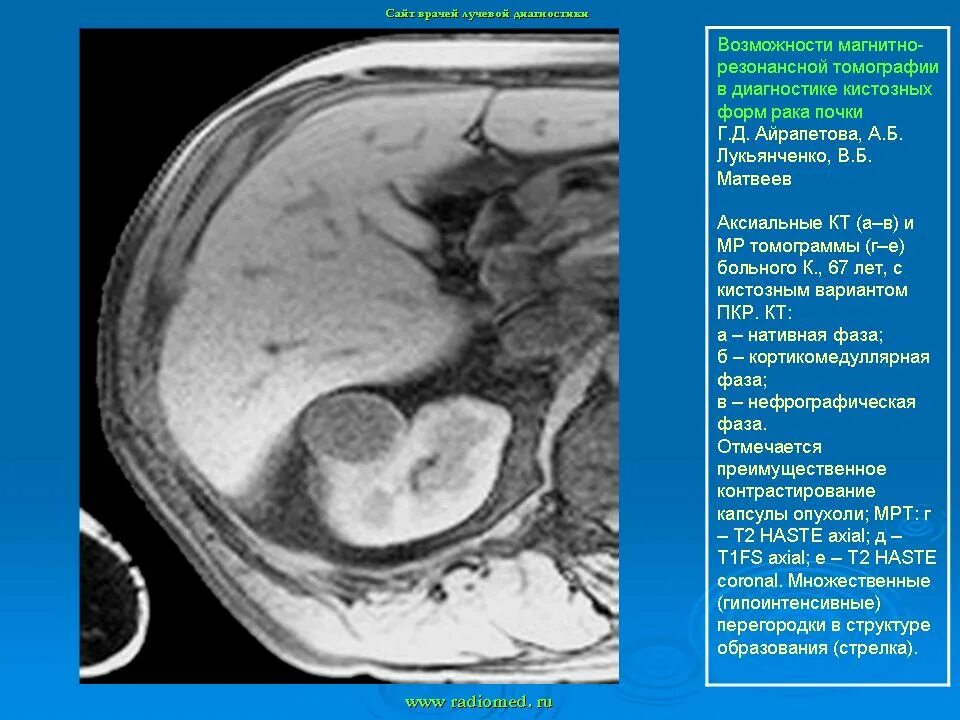

Обследование почек мрт